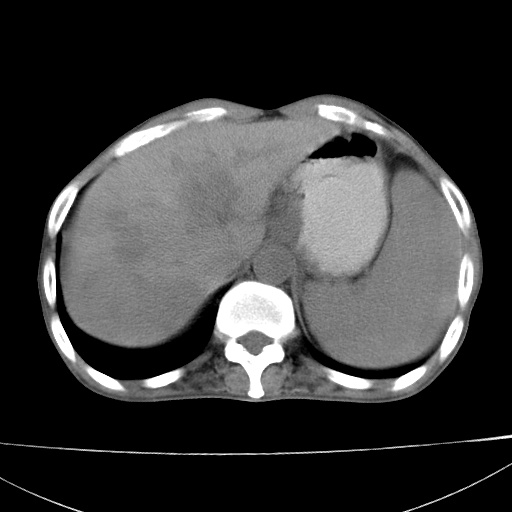

患者 男  41岁,右上腹痛伴腹泻10天,8年前有乙肝,本次b超查肝右叶占位来做ct ,请会诊!

肝硬化\\脾大\\门静脉高压,胃底静脉曲张可能性大.肝右叶肝癌肝内转移,建议增强.左侧小结石.

支持肝癌伴肝内转移,脾大,门静脉高压,胃底静脉曲张。

1)考虑肝癌;建议行ct增强扫描检查。2)脾大,门静脉高压,胃底静脉曲张。3)左肾小结石。

1)考虑肝癌及门脉瘤栓,建议行ct增强扫描检查。2)脾大,门静脉高压,胃底静脉曲张。3)左肾小结石。

结合病史;考虑肝癌。门静脉高压,脾大。胃底静脉曲张。

1)考虑肝癌;2)脾大,门静脉高压,胃底静脉曲张。3)左肾小结石。建议行ct增强扫描检查。